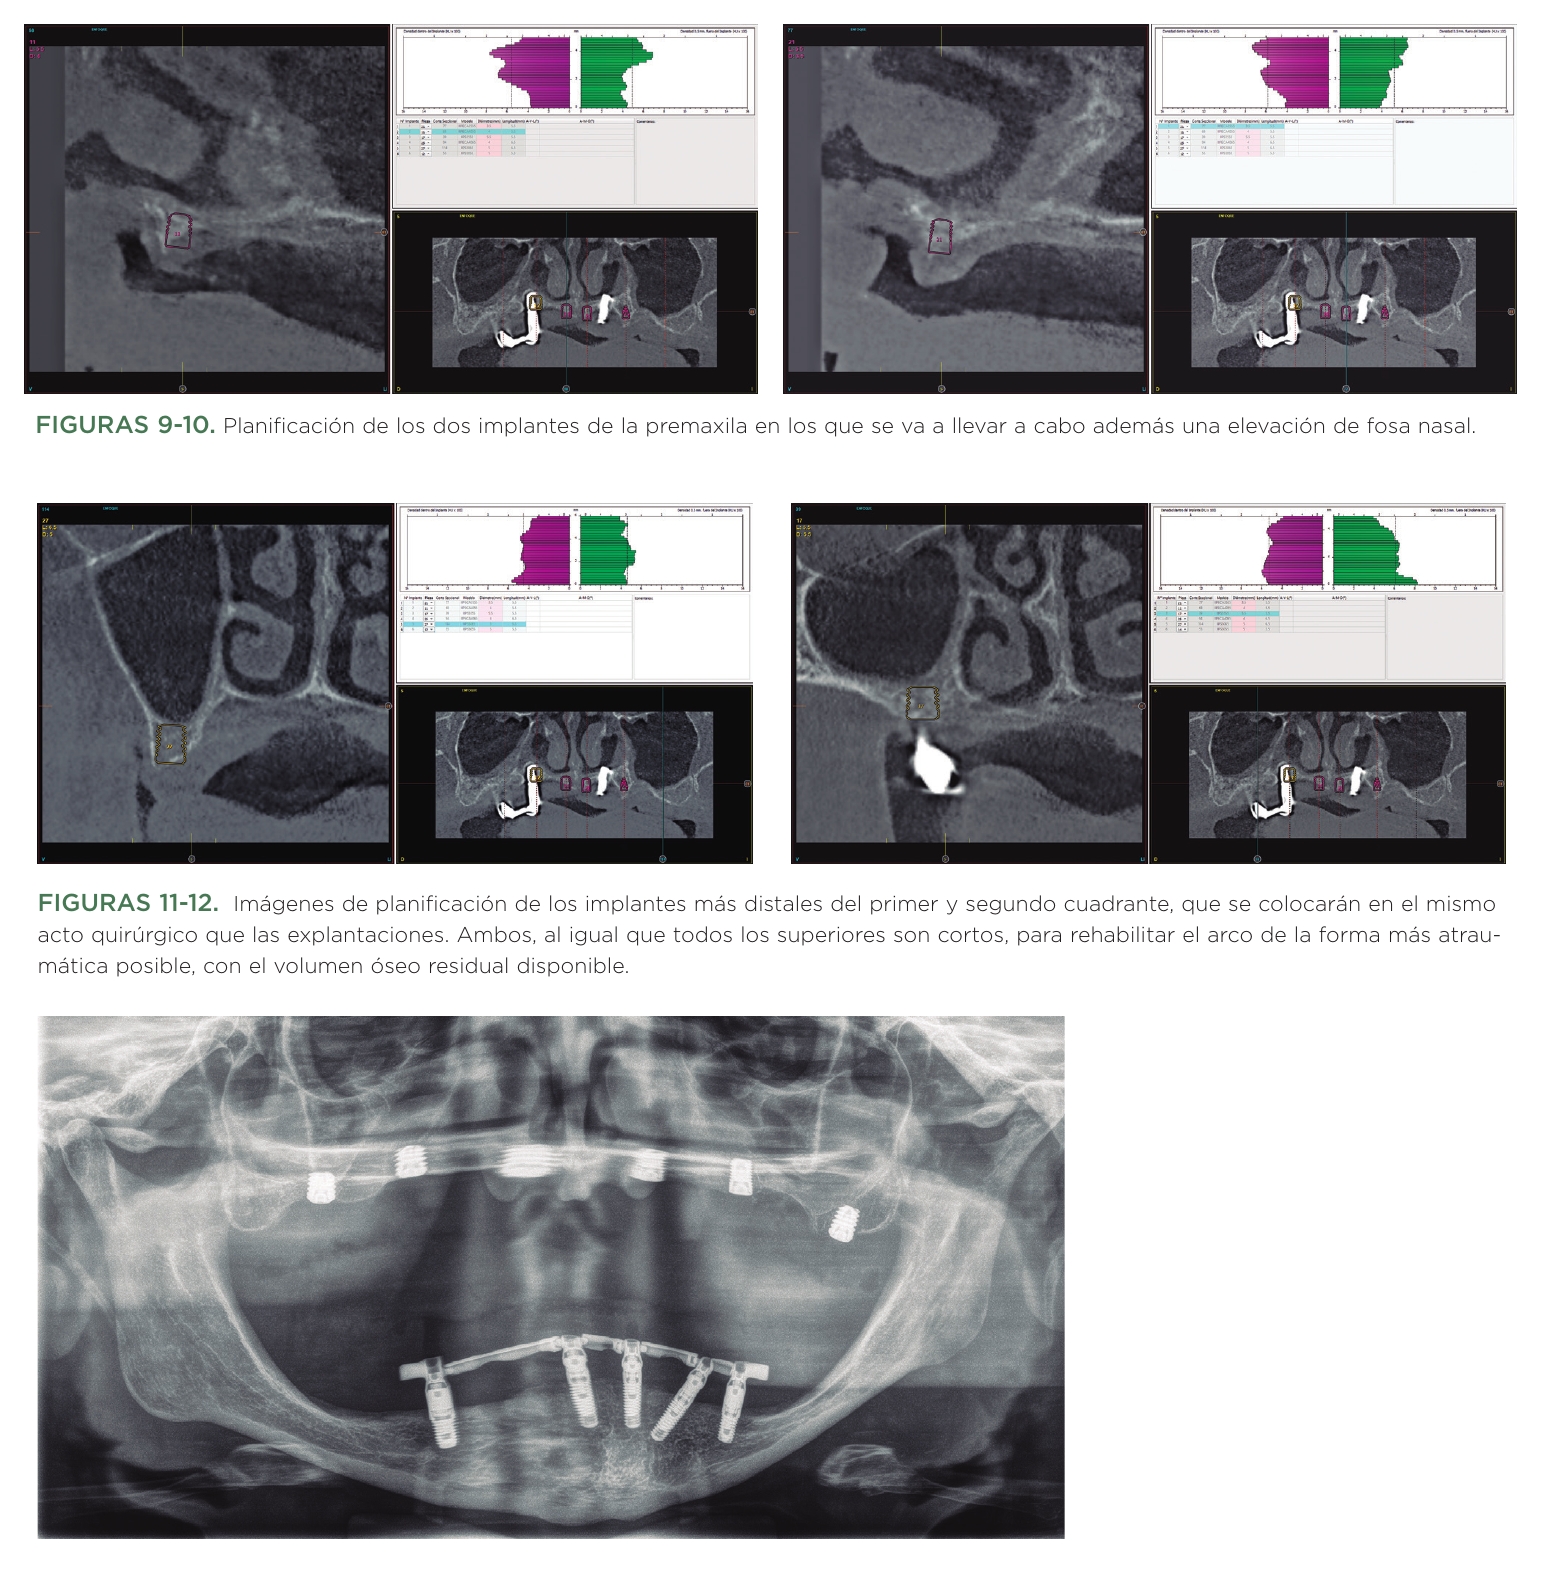

En la planificación superior, observamos una atrofia extrema en la zona de la premaxila, que nos hace planificar dos implantes extra-cortos de 5,5 y 6,5 mm unidos al procedimiento de elevación de fosa nasal atraumático. Este procedimiento ha sido descrito por nuestro grupo de estudio20 y se lleva a cabo mediante una fresa de corte frontal de igual forma que la elevación de seno transcrestal (figuras 9 y 10).

En el primer cuadrante, se van a realizar las explantaciones atraumáticas de los dos implantes remanentes y en el mismo procedimiento quirúrgico se colocará un implante en la zona correspondiente a la pieza 16 y otro en el lecho post-explantación del implante más mesial, ambos cortos, al igual que los que se planifican en el segundo cuadrante por detrás del implante remanente afectado por periimplantitis que será extraído en la misma cirugía (figuras 11 y 12). Rehabilitando de nuevo el maxilar superior con implantes cortos empleándose la técnica de elevación transcrestal en las zonas posteriores y de elevación de fosa nasal en la anterior se logra un abordaje mínimamente invasivo del caso, con una resolución sencilla en una única fase quirúrgica. En la cirugía se realizan todas las explantaciones (incluida una en la mandíbula en posición 45 por presentar pérdida ósea crateriforme) además de la colocación de los nuevos implantes superiores e inferiores. En la mandíbula podemos además llevar a cabo una prótesis de carga progresiva uniendo tres de los implantes antiguos a los dos nuevos, pero con la colocación de transepiteliales (figura 13).